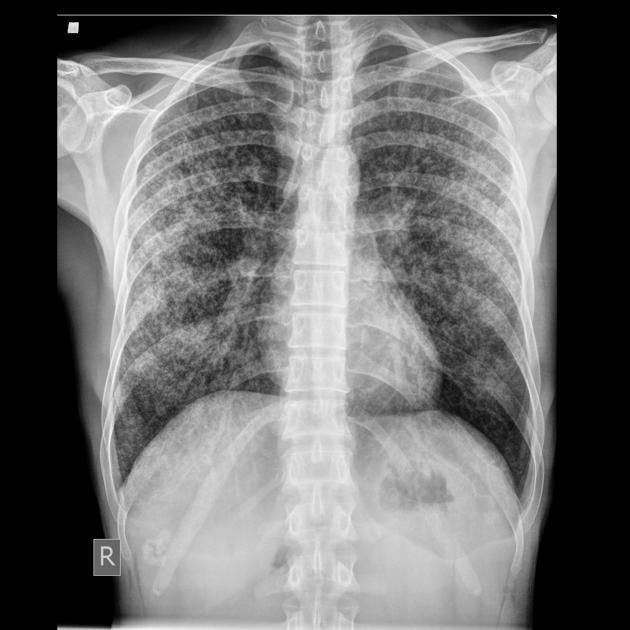

CXR

may be normal bilateral hilar enlargement consolidation, cavitation, fibrosis and calcification